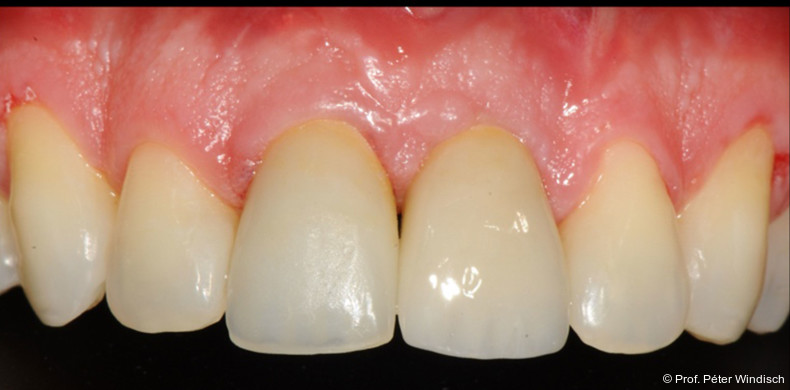

Das Emergenzprofil wurde mit einer polierten, eindeutig konvexen „S-Kurve“ neu gestaltet (Abb. 9+10). Diese neu entwickelte Geometrie schafft ausreichend Raum für die Weichgeweberegeneration, stützt den Gingivasaum, ohne durch überkonturierte („bulky“) Formen Nischen für Plaque zu schaffen. Die Synergie aus einer biokompatiblen Materialoberfläche (polierte Keramik) und einer reinigungsfähigen Anatomie stellt sicher, dass die Ergebnisse der submarginalen Instrumentierung dauerhaft stabil bleiben und der Patient die Stelle effektiv mit Interdentalbürsten pflegen kann.

Der Patient wurde angewiesen, zwei Stunden lang nichts zu essen oder zu trinken, sowie für die nächsten 24 Stunden keine Zahnreinigung oder CHX-haltige Mundspüllösungen und für die nächsten zwei Tage keine Interdentalbürsten zu verwenden.  Bei der Reevaluation nach sechs Monaten zeigte sich eine deutliche Verbesserung der periimplantären Gewebesituation. (Abb. 10+11). Durch die Behandlung konnten die klinischen Parameter deutlich verbessert werden. Die periimplantäre Sondierungstiefe wurde signifikant auf ein physiologische Taschentiefe reduziert, es war zudem keine Blutung auf Sondierung (BOP) mehr vorhanden.

Das Weichgewebe präsentierte sich klinisch entzündungsfrei. Radiologisch zeigte sich nach zwölf Monaten eine deutliche Verbesserung der knöchernen Situation im Sinne einer Auffüllung des knöchernen Defekts (Abb. 12). Das Ergebnis konnte durch regelmäßige Implantat-Maintenancetermine stabilisiert werden. Abbildung 13 zeigt die ausgereifte periimplantäre Hartgewebesituation.